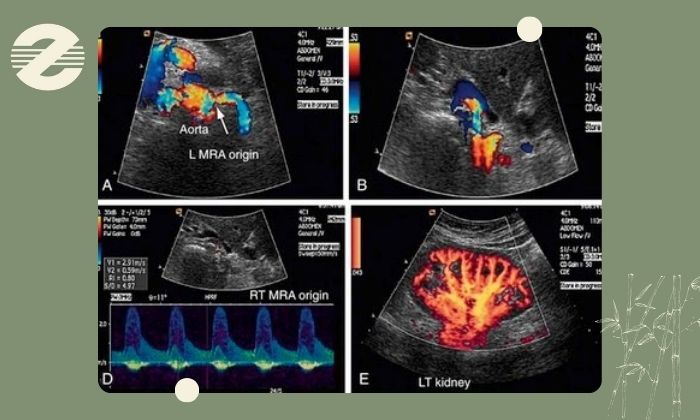

مرکز تصویربرداری پزشکی زعیم تحت مدیریت دکتر علیرضا سرزعیم (فلوشیپ مداخلهای) با همکاری دکتر سمیه زارعی و دکتر مهرناز راسته خدمات تخصصی سونوگرافی رنگی داپلر را با بهرهگیری از جدیدترین فناوریها ارائه میکند. این تیم با تسلط بر تکنیکهای روز دنیا قادر است طیف وسیعی از بیماریهای عروقی و قلبی را تشخیص دهد و به کمک گزارشهای دقیق درمان بیماران را تسهیل نماید.تجهیزات پیشرفته مرکز

در این مرکز دستگاههای نسل جدید سونوگرافی مطابق استانداردهای جهانی مورد استفاده قرار میگیرند. این تجهیزات قادرند در مدت زمان کوتاه تصاویری با وضوح بالا از جریان خون در عروق بدن تهیه کرده و با تحلیل پیشرفته دادهها جزئیترین اختلالات عروقی و قلبی را نمایان سازند.اطلاعات جمعآوری شده توسط تیم پزشکی مرکز بهصورت تخصصی تفسیر و گزارش میشوند تا بهترین مسیر درمان برای هر بیمار انتخاب شود.